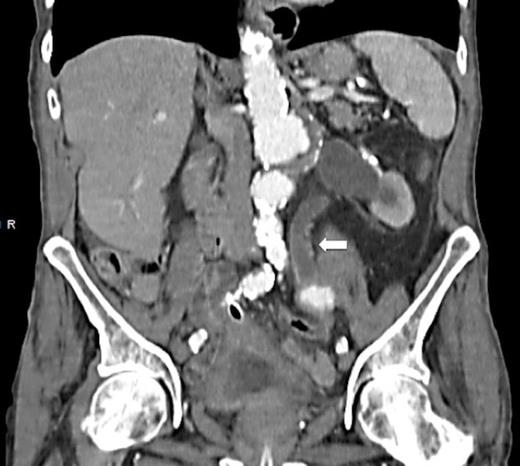

A 90 year old gentleman was admitted with haematuria and acute painful urinary clot retention. Prior to admission, he reported a 6 month history of intermittent visible haematuria. His past medical history included Duke’s A rectal carcinoma, hypertension and ischaemic heart disease. His haemoglobin count was 8.7g/dL and his renal function was normal. He was catheterised using a 3-way catheter with supplementary bladder washouts and received a 2 unit blood transfusion. Abdominal ultrasound revealed moderate left hydronephrosis. A CT urogram detected a 48mm infra-renal aortic aneurysm with bilateral iliac artery aneurysms – 33mm left, 31mm right. This scan also identified moderate to severe hydronephrosis on the left side with hydroureter extending down to the level of the iliac aneurysm (Fig. 1 & 2). There was no obvious fistula between the left ureter and the iliac aneurysm.

CT scan demonstrating hydronephrosis and hydroureter on the left side